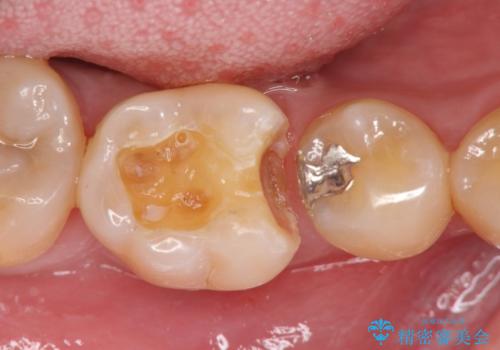

歯の神経を残す、丁寧な虫歯の除去

- 銀歯の劣化、歯のしみる症状の改善を求めて来院されました。

マイクロスコープ、拡大鏡を用いて治療を行うことで虫歯を取り切ることと必要以上に歯を削らず真剣を温存することのできる確率が高まります。

虫歯治療後の予後をより良くするために、虫歯を取り切ること精密な修復物の装着が必須となります。